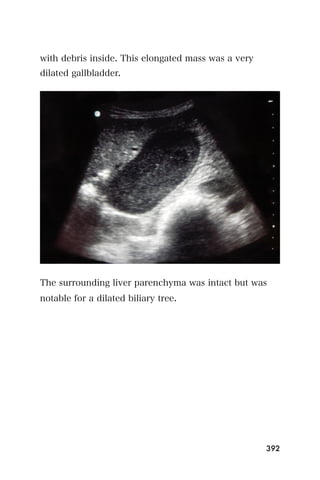

method to assess patients with suspected DVT.

Background

Before the widespread use of ultrasound, patients with